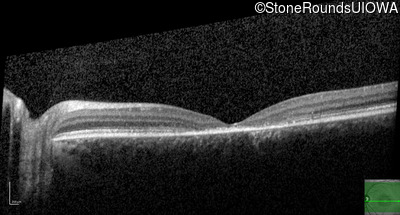

Optical Coherence Tomography - Right - 10/125 -1

Exemplar / OCT Stack